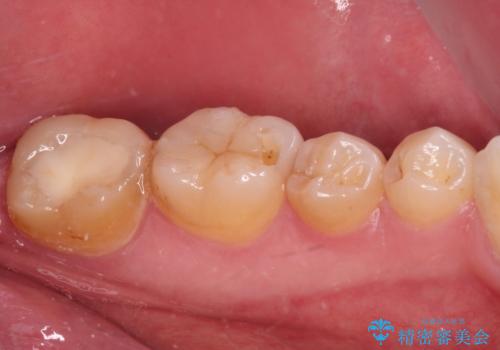

長期海外赴任が近いとのことで、出発に間に合うようにアポイントを調整して治療を進めて行きました。

中途半端に歯冠の見えている親知らずもあったため、そちらも出発前に抜歯を行いました。